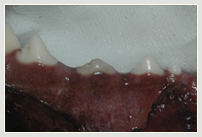

Zahnfraktur Katze Zahnfraktur Katze vorn Vergleich Katze nach Wurzelbehandlung u. Plombe